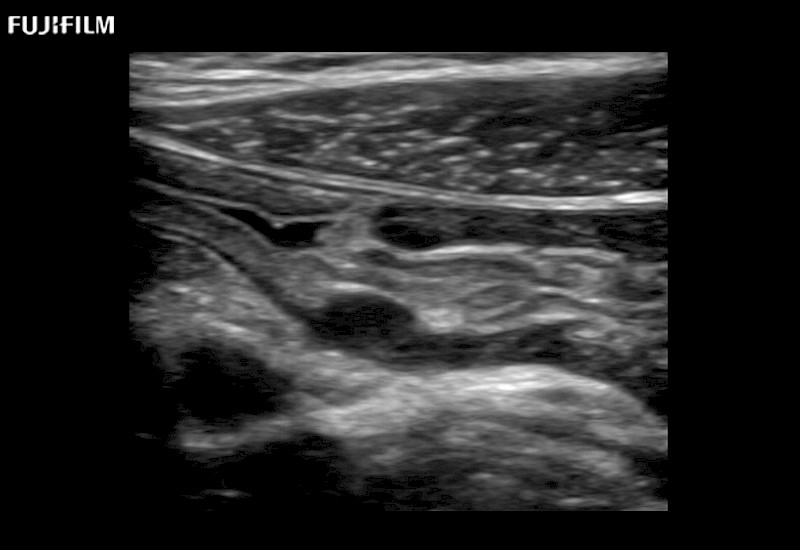

The ARIETTA 650 DI combines trusted Fujifilm Healthcare technologies and features tailored for surgical oncology.

Designed to meet the demands of surgeons, the ARIETTA 650 DI offers precise guidance. Its advanced capabilities and large, intuitive display offer accurate and efficient care in operating rooms and specialized surgical settings.